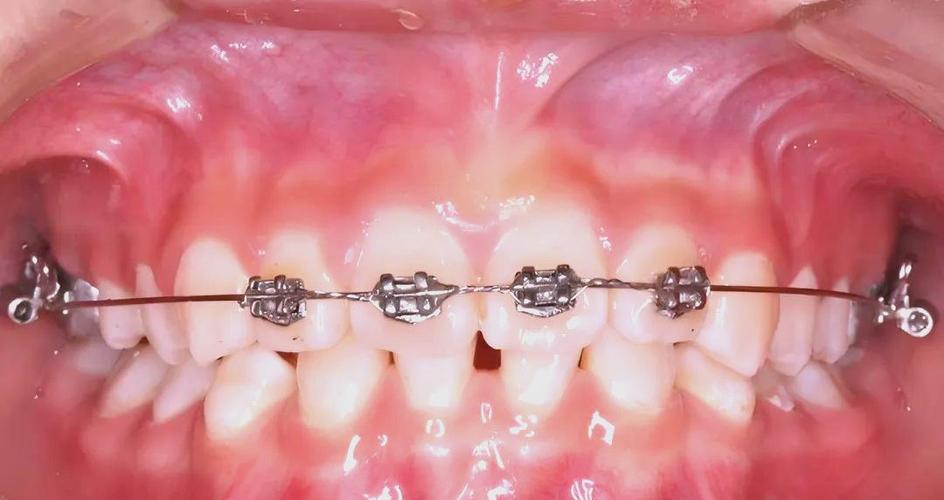

工具与材料方面,20年前正畸的“硬件”基础较为简陋,托槽以金属材质为主(如不锈钢),体积较大,边缘粗糙易刺激口腔黏膜;陶瓷托槽虽已出现,但脆性高、易脱落,且价格昂贵,仅少数患者选用,弓丝材料以镍钛圆丝(用于排齐阶段)、不锈钢方丝(关闭间隙、精细调整)为主,热激活镍钛丝(形状记忆合金)应用较少,持续加力效果不稳定,粘接材料多为化学固化树脂,需手动混合调配,粘接强度弱,托槽脱落率高(平均每颗托槽脱落率约10%-15%),常延长治疗时间,取模依赖藻酸盐印模材料,需等待石膏模型凝固后手工修整,模型精度有限,数字化口扫技术尚未普及,头影测量依赖X光片手工描点计算,误差较大,方案设计更多依赖医生经验而非数据支持。

临床操作上,20年前正畸治疗周期普遍较长(平均2.5-3年),复诊间隔4-6周(因弓丝变形、托槽脱落需频繁调整),拔牙矫治比例较高(约40%-50%),因非拔牙矫治的扩弓、推磨牙等手段有限,且对骨性问题的干预能力不足,患者体验方面,“钢牙”特征明显:金属托槽和结扎丝易刮伤口腔,清洁困难导致龋齿、牙龈炎高发;治疗全程需患者严格忌口(避免硬、黏食物),依从性要求高,医生工作强度大,每次复诊需1-2小时完成弓丝更换、结扎、调整,效率低下。